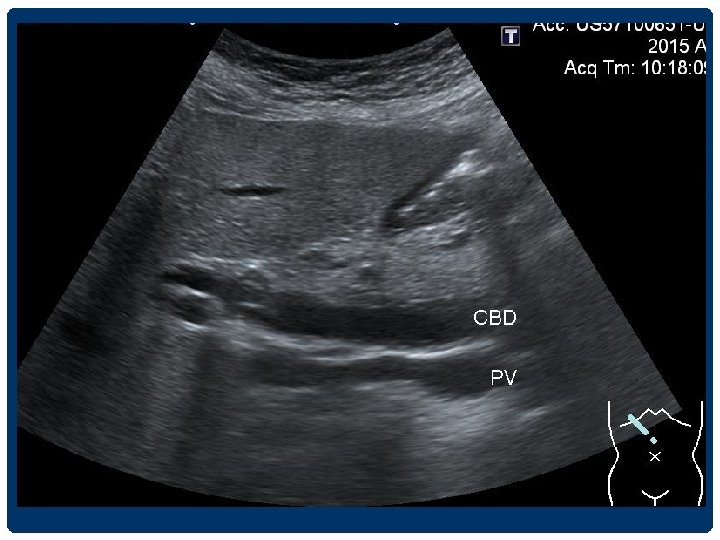

DILATED CBD

BILIARY DILATATION Extrahepatic duct - CHD 4 -5 mm - CBD วดจากขอบดานในของดานหนงไปอกดานหน ง 4 -6 mm 6 -7 mm equivocal >8 mm indicate ductal dilatation • Elderly patients and in postcholecystectomy patients อาจพบ common duct dilatation ไดถง 9 -10 mm • Acute, intermittent, and partial obstruction